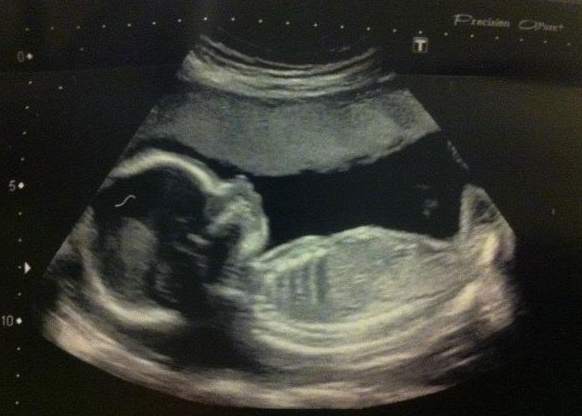

20 Week Scan